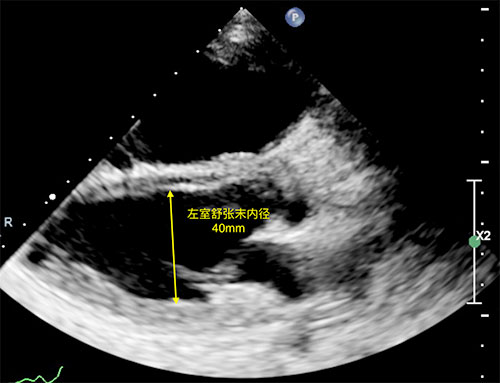

患者出院前超声心动图,示左室舒张末内径恢复至40mm